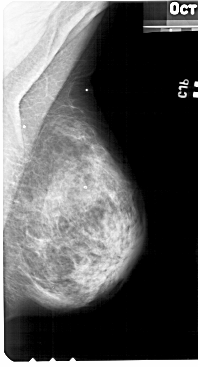

A_1427_1.RIGHT_MLO

RIGHT_MLO LINES 5491 PIXELS_PER_LINE 2956 BITS_PER_PIXEL 12 RESOLUTION 43.5 NON_OVERLAY